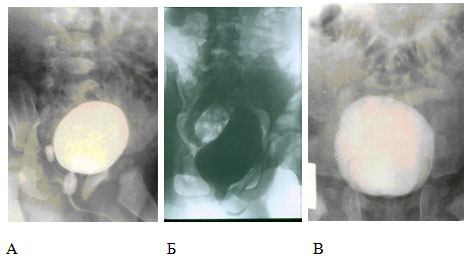

Диагностика

Диагностический алгоритм детрузорно-сфинктерной диссинергии включает: общий анализ мочи, посев мочи на стерильность с антибиотикограммой, заполнение анкеты IPSS, ультразвуковое исследование мочевого пузыря с определением объема остаточной мочи и комплексное уродинамическое обследование.